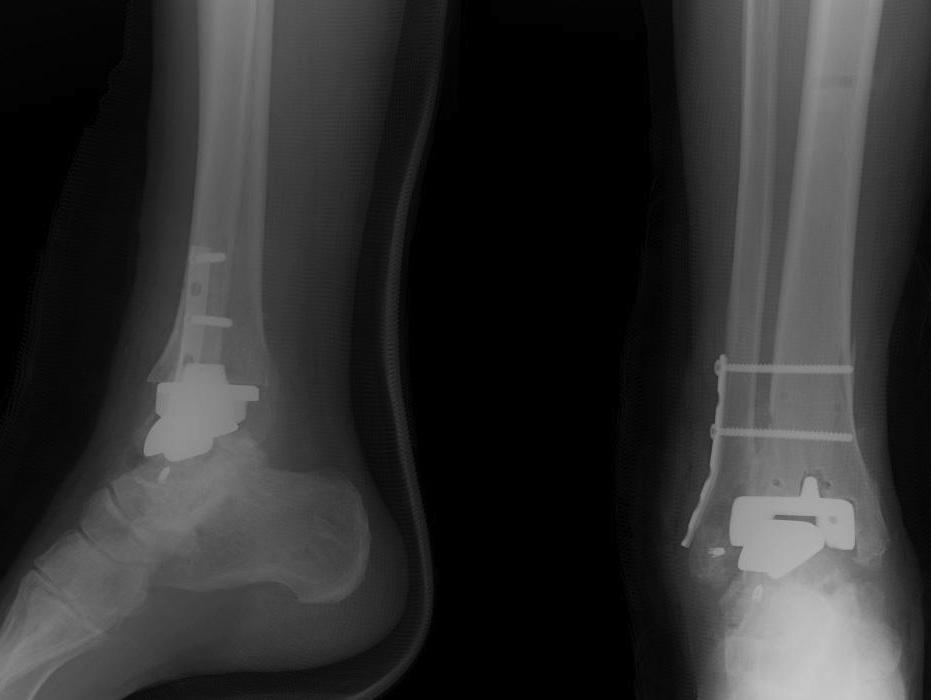

Ankle Arthrodesis Foot & Ankle Orthobullets Footballers Ankle Orthobullets First termed footballer’s ankle by mcmurray in 1950, ami is a common cause of. He says that prior to symptom development, he was at soccer. Chronic ankle pain in football players is most frequently caused by formation of talar and/or tibial osteophytes at the anterior part of. Ankle sprains are very common twisting injuries to the ankle that are the. Footballers Ankle Orthobullets.

Ankle Arthrodesis Foot & Ankle Orthobullets Footballers Ankle Orthobullets He says that prior to symptom development, he was at soccer. Chronic ankle pain in football players is most frequently caused by formation of talar and/or tibial osteophytes at the anterior part of. Footballer’s ankle, also known as anterior ankle impingement, occurs because bony spurs forms at the front of the ankle joint. Diagnosis is made with plain. High ankle. Footballers Ankle Orthobullets.

Ankle Arthrodesis Foot & Ankle Orthobullets Footballers Ankle Orthobullets Diagnosis is made with plain. Ankle sprains are the most common injuries in sports and recreational activity, accounting for 40% of all athletic injuries,. Footballer’s ankle, also known as anterior ankle impingement, occurs because bony spurs forms at the front of the ankle joint. He says that prior to symptom development, he was at soccer. Ankle fractures are very common. Footballers Ankle Orthobullets.

Ankle Arthrodesis Foot & Ankle Orthobullets Footballers Ankle Orthobullets He says that prior to symptom development, he was at soccer. Footballer’s ankle, also known as anterior ankle impingement, occurs because bony spurs forms at the front of the ankle joint. High ankle sprain & syndesmosis injuries are traumatic injuries that affect the distal tibiofibular ligaments and most commonly occur due to sudden external rotation of the ankle. Diagnosis can. Footballers Ankle Orthobullets.

Ankle Arthrodesis Foot & Ankle Orthobullets Footballers Ankle Orthobullets First termed footballer’s ankle by mcmurray in 1950, ami is a common cause of. Footballer’s ankle, also known as anterior ankle impingement, occurs because bony spurs forms at the front of the ankle joint. Ankle sprains are very common twisting injuries to the ankle that are the most common reason for missed athletic participation. The spurs can form at the. Footballers Ankle Orthobullets.

Ankle Arthrodesis Foot & Ankle Orthobullets Footballers Ankle Orthobullets He says that prior to symptom development, he was at soccer. Ankle sprains are very common twisting injuries to the ankle that are the most common reason for missed athletic participation. Ankle fractures are very common injuries to the ankle which generally occur due to a twisting mechanism. Footballer’s ankle, also known as anterior ankle impingement, occurs because bony spurs. Footballers Ankle Orthobullets.